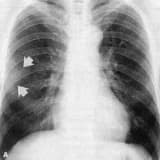

Bypass əməliyyatı açıq ürək əməliyyatıdır. Bypass ümumi anesteziya ilə edilən əməliyyatdır və ortalama əməliyyat müddəti 4 saat çəkir. Döş sümüyünün kəsilməsi ilə ürəyə çatılır. Əməliyyat zamanı ümumiyyətlə ürəyin dayandırılması lazımdır. Ürəyin işləmədiyi bu zaman ürəyin və ağciyərlərin işini yerinə yetirən ürək-ağciyər maşını istifadə olunur. Bədənin qana olan tələbatı ödənilir və qan bu aparatla təmizlənir. Bəzi hallarda ürəyi dayandırmadan bu əməliyyatı edə bilərik. Bu cür cərrahi əməliyyatlara nasosdan kənar və ya döyünən ürək deyilir.

Bypassdan, yəni körpü əmələ gəlmə prosesindən sonra yenidən ürək əməliyyat edilir və ürək-ağciyər maşını dayandırılır və qan dövranı yenidən ürəyə buraxılır. Lazımı nəzarətlər edildikdən sonra sternum güclü tellər ilə birləşdirilir. Xəstənin əməliyyatı bitdikdən sonra xəstə reanimasiya şöbəsinə aparılır. Xəstənin vəziyyətindən asılı olaraq 1-2 gün reanimasiya şöbəsində, sonra isə 4-5 gün xidmət otağında müşahidə edilir. Xəstənin istədiyi kimi gəzə, televizora baxa və yaxınları ilə danışa biləcəyi otaqda; Xəstəxana xaricində uyğunlaşma təmin edilərək normal həyata qaytarılır.